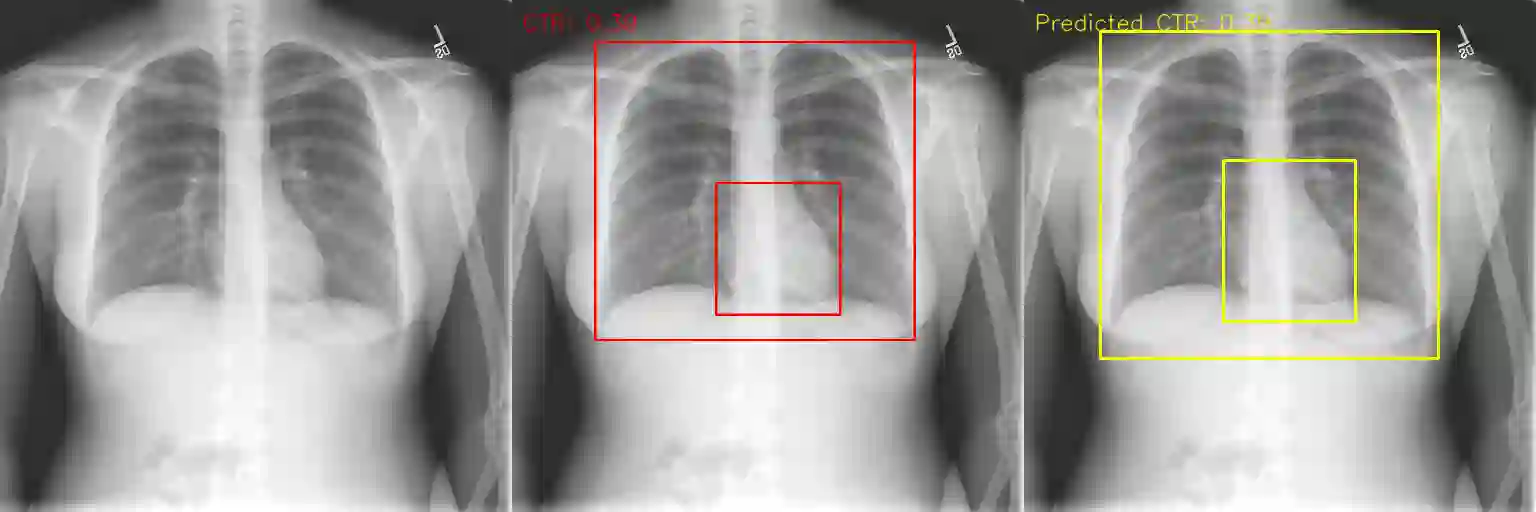

We propose an automated method based on deep learning to compute the cardiothoracic ratio and detect the presence of cardiomegaly from chest radiographs. We develop two separate models to demarcate the heart and chest regions in an X-ray image using bounding boxes and use their outputs to calculate the cardiothoracic ratio. We obtain a sensitivity of 0.96 at a specificity of 0.81 with a mean absolute error of 0.0209 on a held-out test dataset and a sensitivity of 0.84 at a specificity of 0.97 with a mean absolute error of 0.018 on an independent dataset from a different hospital. We also compare three different segmentation model architectures for the proposed method and observe that Attention U-Net yields better results than SE-Resnext U-Net and EfficientNet U-Net. By providing a numeric measurement of the cardiothoracic ratio, we hope to mitigate human subjectivity arising out of visual assessment in the detection of cardiomegaly.